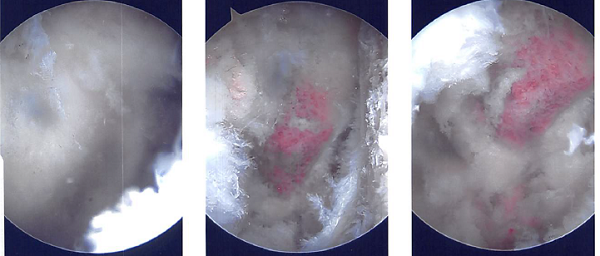

A beanbag held the position, and all of the bone prominences were well-padded. Behind the posterolateral corner of the acromion, a surgical incision was made. The glenohumeral joint was penetrated with the scope. There was a glenohumeral joint examination.

The labral hole was present. Labral degenerations were removed by shaving. The posterior labrum had degeneration, which was cleared out by shaving. There was subacromial bursitis.

Using a shaver, a thorough bursectomy was performed. It was created a lateral portal. The acromion was frayed and had a type 2 (curved configuration) configuration.

Acromioplasty was decided upon. After cleaning with a heat wand and a bur, acromioplasty was carried out. The AC joint was checked after a comprehensive acromioplasty and found to be degenerating. Excision of the distal clavicle was planned. The distal clavicle was removed using a wand and then a bur.

The distal clavicle’s last centimeter was removed. Final images were captured and stored. Nylon #4-0 was used for closure. After being extubated, the patient was taken to the recovery area.